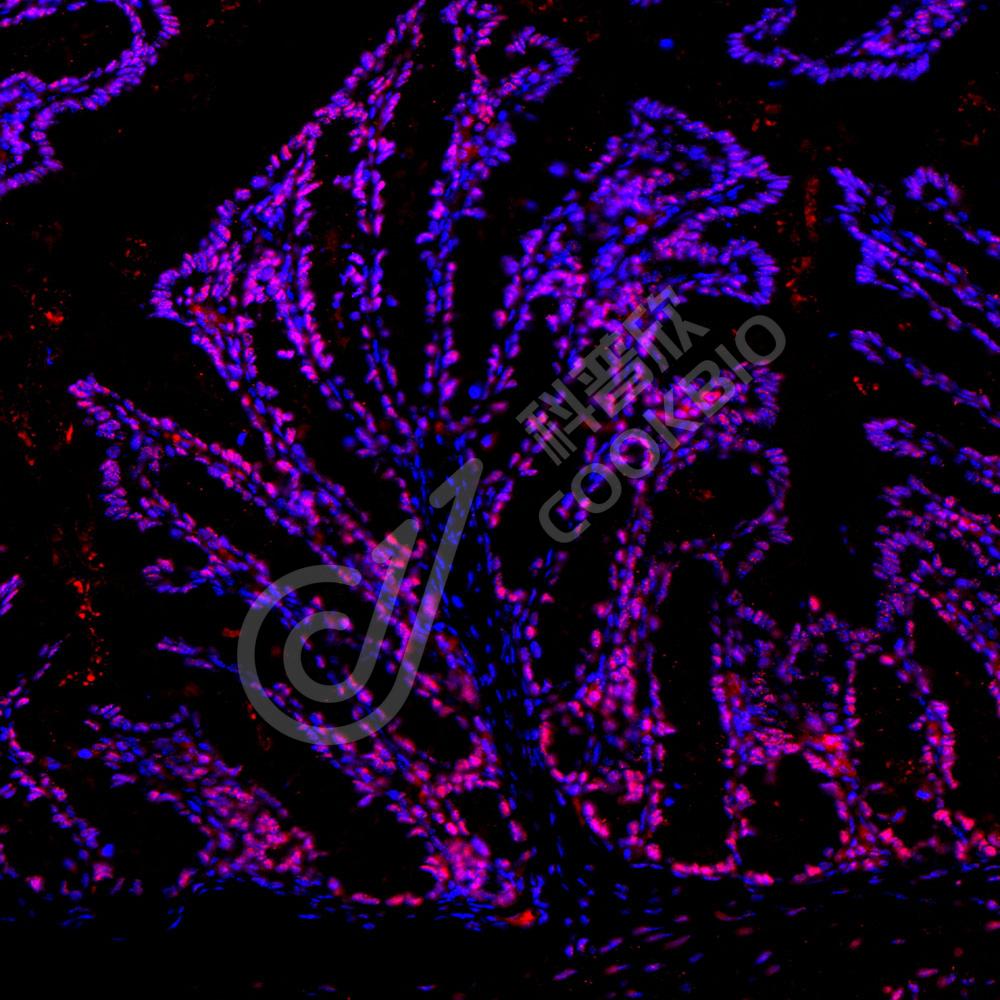

IF检测PMS2蛋白(货号 K2360003)(红色).

样品: 小鼠结肠, 4%多聚甲醛 (货号KSG1101) 固定12-24小时.

抗原修复: 柠檬酸抗原修复液(干粉, pH 6.0) (KSG1201), 高压锅均匀喷气计时2分钟.

封闭: 3% BSA(货号KSGC305010)的PBS溶液, 室温孵育30分钟.

—抗: 1: 800稀释, 4℃ 孵育过夜.

二抗: Cy3标记山羊抗小鼠IgG (H+L) (货号KB63903), 1: 300稀释, 室温孵育1小时.